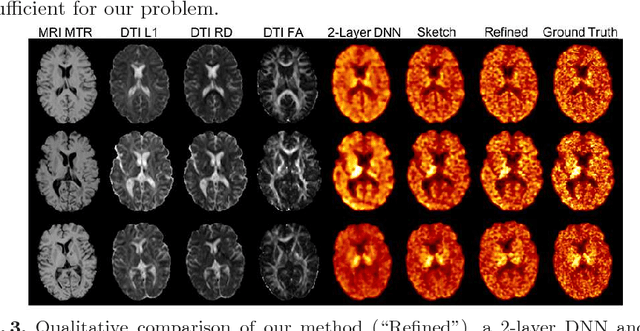

Abstract:Multiple sclerosis (MS) is a demyelinating disease of the central nervous system (CNS). A reliable measure of the tissue myelin content is therefore essential for the understanding of the physiopathology of MS, tracking progression and assessing treatment efficacy. Positron emission tomography (PET) with $[^{11} \mbox{C}] \mbox{PIB}$ has been proposed as a promising biomarker for measuring myelin content changes in-vivo in MS. However, PET imaging is expensive and invasive due to the injection of a radioactive tracer. On the contrary, magnetic resonance imaging (MRI) is a non-invasive, widely available technique, but existing MRI sequences do not provide, to date, a reliable, specific, or direct marker of either demyelination or remyelination. In this work, we therefore propose Sketcher-Refiner Generative Adversarial Networks (GANs) with specifically designed adversarial loss functions to predict the PET-derived myelin content map from a combination of MRI modalities. The prediction problem is solved by a sketch-refinement process in which the sketcher generates the preliminary anatomical and physiological information and the refiner refines and generates images reflecting the tissue myelin content in the human brain. We evaluated the ability of our method to predict myelin content at both global and voxel-wise levels. The evaluation results show that the demyelination in lesion regions and myelin content in normal-appearing white matter (NAWM) can be well predicted by our method. The method has the potential to become a useful tool for clinical management of patients with MS.